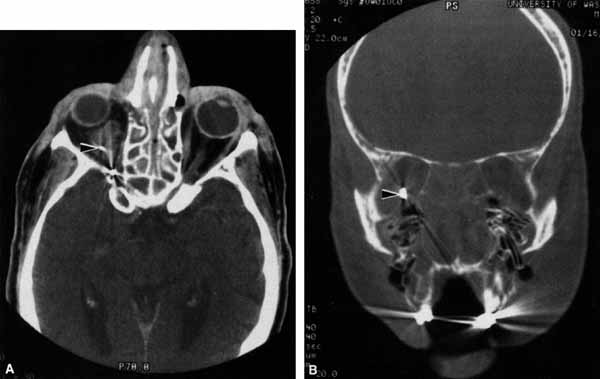

Fig. 19 A. A patient underwent endoscopic exploration of the right ethmoid and maxillary sinus for persistent epistaxis. Postoperatively the patient demonstrates right proptosis, restricted extraocular movements of the right eye, and a dilated right pupil. Instillation of 0.1% pilocarpine resulted in miosis on the right and no change on the left. Computed tomography (CT) shows a vessel clip lateral to the optic nerve (arrow), near the position of the ciliary ganglion. B. Coronal CT scan showing the clip lateral to the optic nerve (arrow).

CASE 4

A 52-year-old woman presented with diplopia when looking to her right. She had noted a red right eye for the past 3 months (Fig. 25A). Visual acuity was 20/20 in both eyes and the pupils were normal. The right eye was limited in abduction. Forced duction testing showed abduction of the right eye to be restricted. Intraocular pressures were 23 mm Hg OD, and 15 mm HG OS. CT showed a dilated right superior ophthalmic vein (Fig. 25B) which was shown to be caused by a dural cavernous fistula. The right medial rectus muscle was also enlarged (Fig. 25C) because of blood engorgement, reducing muscle compliance, which accounted for the restricted abduction.

Fig. 25 A. A 52-year-old woman with a right dural cavernous fistula demonstrates a red right eye. B. Computed tomography (CT) scan demonstrates dilated right superior ophthalmic vein (arrow) secondary to the dural cavernous fistula. C. Enlarged right medial rectus muscle (arrow).

Carotid cavernous fistulas can develop either as a result of trauma or spontaneously.47 A direct carotid cavernous fistula results from a tear in the intracavernous carotid artery with arteriolization of the cavernous sinus and superior orbital vein. Concomitant cranial nerve III, IV, VI, V1 and V2 paresis, elevated intraocular pressure, proptosis, and distention of the deep Tenon's vessels anteriorly (see Fig. 25A) with neuroradiologic evidence of an enlarged superior ophthalmic vein are common (see Fig. 25B). Ophthalmoplegia may also occur on a restrictive basis because of engorgement of the extraocular muscles with blood (see Fig. 25C).36 Dural carotid cavernous fistulas occur where small branches of the intracavernous carotid rupture, allowing access of arterial blood to the cavernous sinus. Typically, the findings are similar to a direct carotid cavernous fistula but of less magnitude. There is no history of trauma, and typically occurs in older persons. However, there is crossover between these two types of carotid cavernous fistula. An excessive ocular pulse tonographically may be helpful in the diagnosis of a carotid cavernous fistula in such cases.48